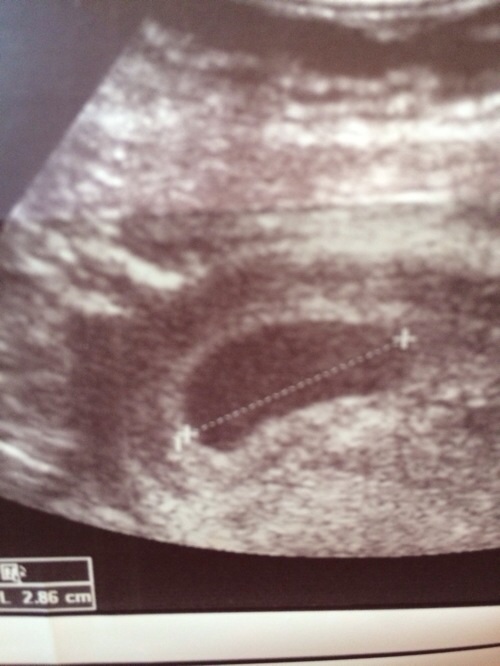

Findet ihr auch, das die FH recht deformiert ist? Der US wurde über die bauchdecke gemacht, war mir zu 10000% sicher das ich ne blasenentzündung hab. War aber alles negativ..

Und lt. dieser Messung wäre die FH innerhalb von 5 Tagen 1,3 cm gewachsen?!?! Des normal?

meine sah auch so aus! ich glaube dieses "nierenförmige" ist normal!

Pusteblume, nach alle meine insg. 4 SS-ten, wo man eine FH sehen konnte, waren die FH´s, je nach Einstellung entweder oval rund, aber auch "unförmig". Das heisst, je nach US-Winkel oder einstellung sieht es anderst aus. US-Bild ist ja 2-Dimensional, FH ist 3D...life.

Ich finde d. Wachstum auch voll in Ordnung! Den Dottersack siht man auf dem Blid auch deutlich!

Dieser Ultraschall hat ne Internistin über die bauchdecke gemacht, nicht mein gyn.. Sie kannte sich damit kaum aus, was natürlich absolut verständlich ist..